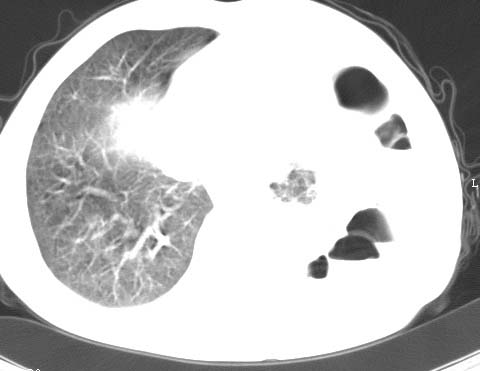

标题: CT10145:男性,30岁,活动后气促2月余.隔疝伴胸腔积液.右上肺结 [打印本页]

男性 病人 30岁,活动后气促2月余.隔疝伴胸腔积液.右上肺结核!

左侧胸腔积液,并胸腔内见多个含液 气组织,并相互重叠。影像特征很特殊,应该是“膈疝”。支持!

左侧膈疝,及左侧胸水,双上肺结核。

支持!左侧膈疝,左侧胸水,双上肺结核。

左侧胸腔包裹性液气胸未除。

左膈疝?